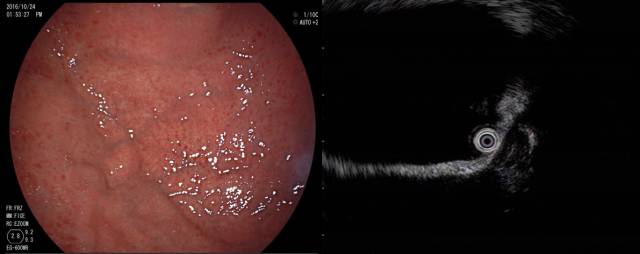

下面病例我们可以看到胃底粘膜下隆起,中央有凹陷(图A),外院CT也考虑胃底间质瘤(图B白色箭头处)。

患者拟手术来我院行超声内镜检查,小探头发现局部胃壁结构欠清,肿块内部为均匀点状回声(图 A),改环扫EUS探查见肿块后方为膈肌,内部为均匀点状回声,考虑副脾,该患者10年前因外伤切除脾脏,故诊断为脾脏切除后副脾代偿性增生外压。

嘱咐患者在我院复查CT检查,请放射科同事局部放大并重建后证实为副脾,故放弃手术。

经典EUS教课书上强调用胃壁五层结的完整性来判断外压,但胃底需倒镜探查,EUS扫描平面很难垂直于病灶且信号衰减明显,识别五层结构困难。此时,观察重点应是病灶的内部回声特点,小间质瘤内部为均匀低回声,这和副脾的点状回声完全不同。打个比方,如果让你分辨一只小老虎(间质瘤)和一个家猫(副脾),你可以通过步态和皮毛来判断(相当于观察胃的五层结构),也可以试图掐一下它们,如果发出“瞄”的声音就是家猫(相当于观察病灶内部的回声特点),下面的病例也是通过上述方法诊断为副脾。

该患者也有脾切除病史,胃镜发现胃底隆起,小探头超声见卵圆形病灶,后方膈肌,内部为典型的均匀点状回声,故诊断副脾,从上述两个病例可以看到,如碰到脾切除后的胃底粘膜下隆起,一定要有副脾增生外压的意识。